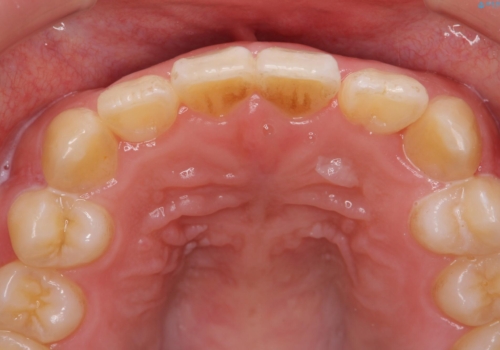

インビザラインの不得意な上顎前歯のねじれの改善を、マウスピース矯正を行う前に前歯のみの部分ワイヤー矯正を行うことで治療期間の短期化を目指します。

上顎前歯のねじれはマウスピースで治りづらいため、マウスピース矯正の治療期間の長期化をきたしやすい歯列不正です。

マススピース矯正を始める前に、部分ワイヤー矯正を行うことで治療の短期間化・良好な仕上がりを達成することができました。